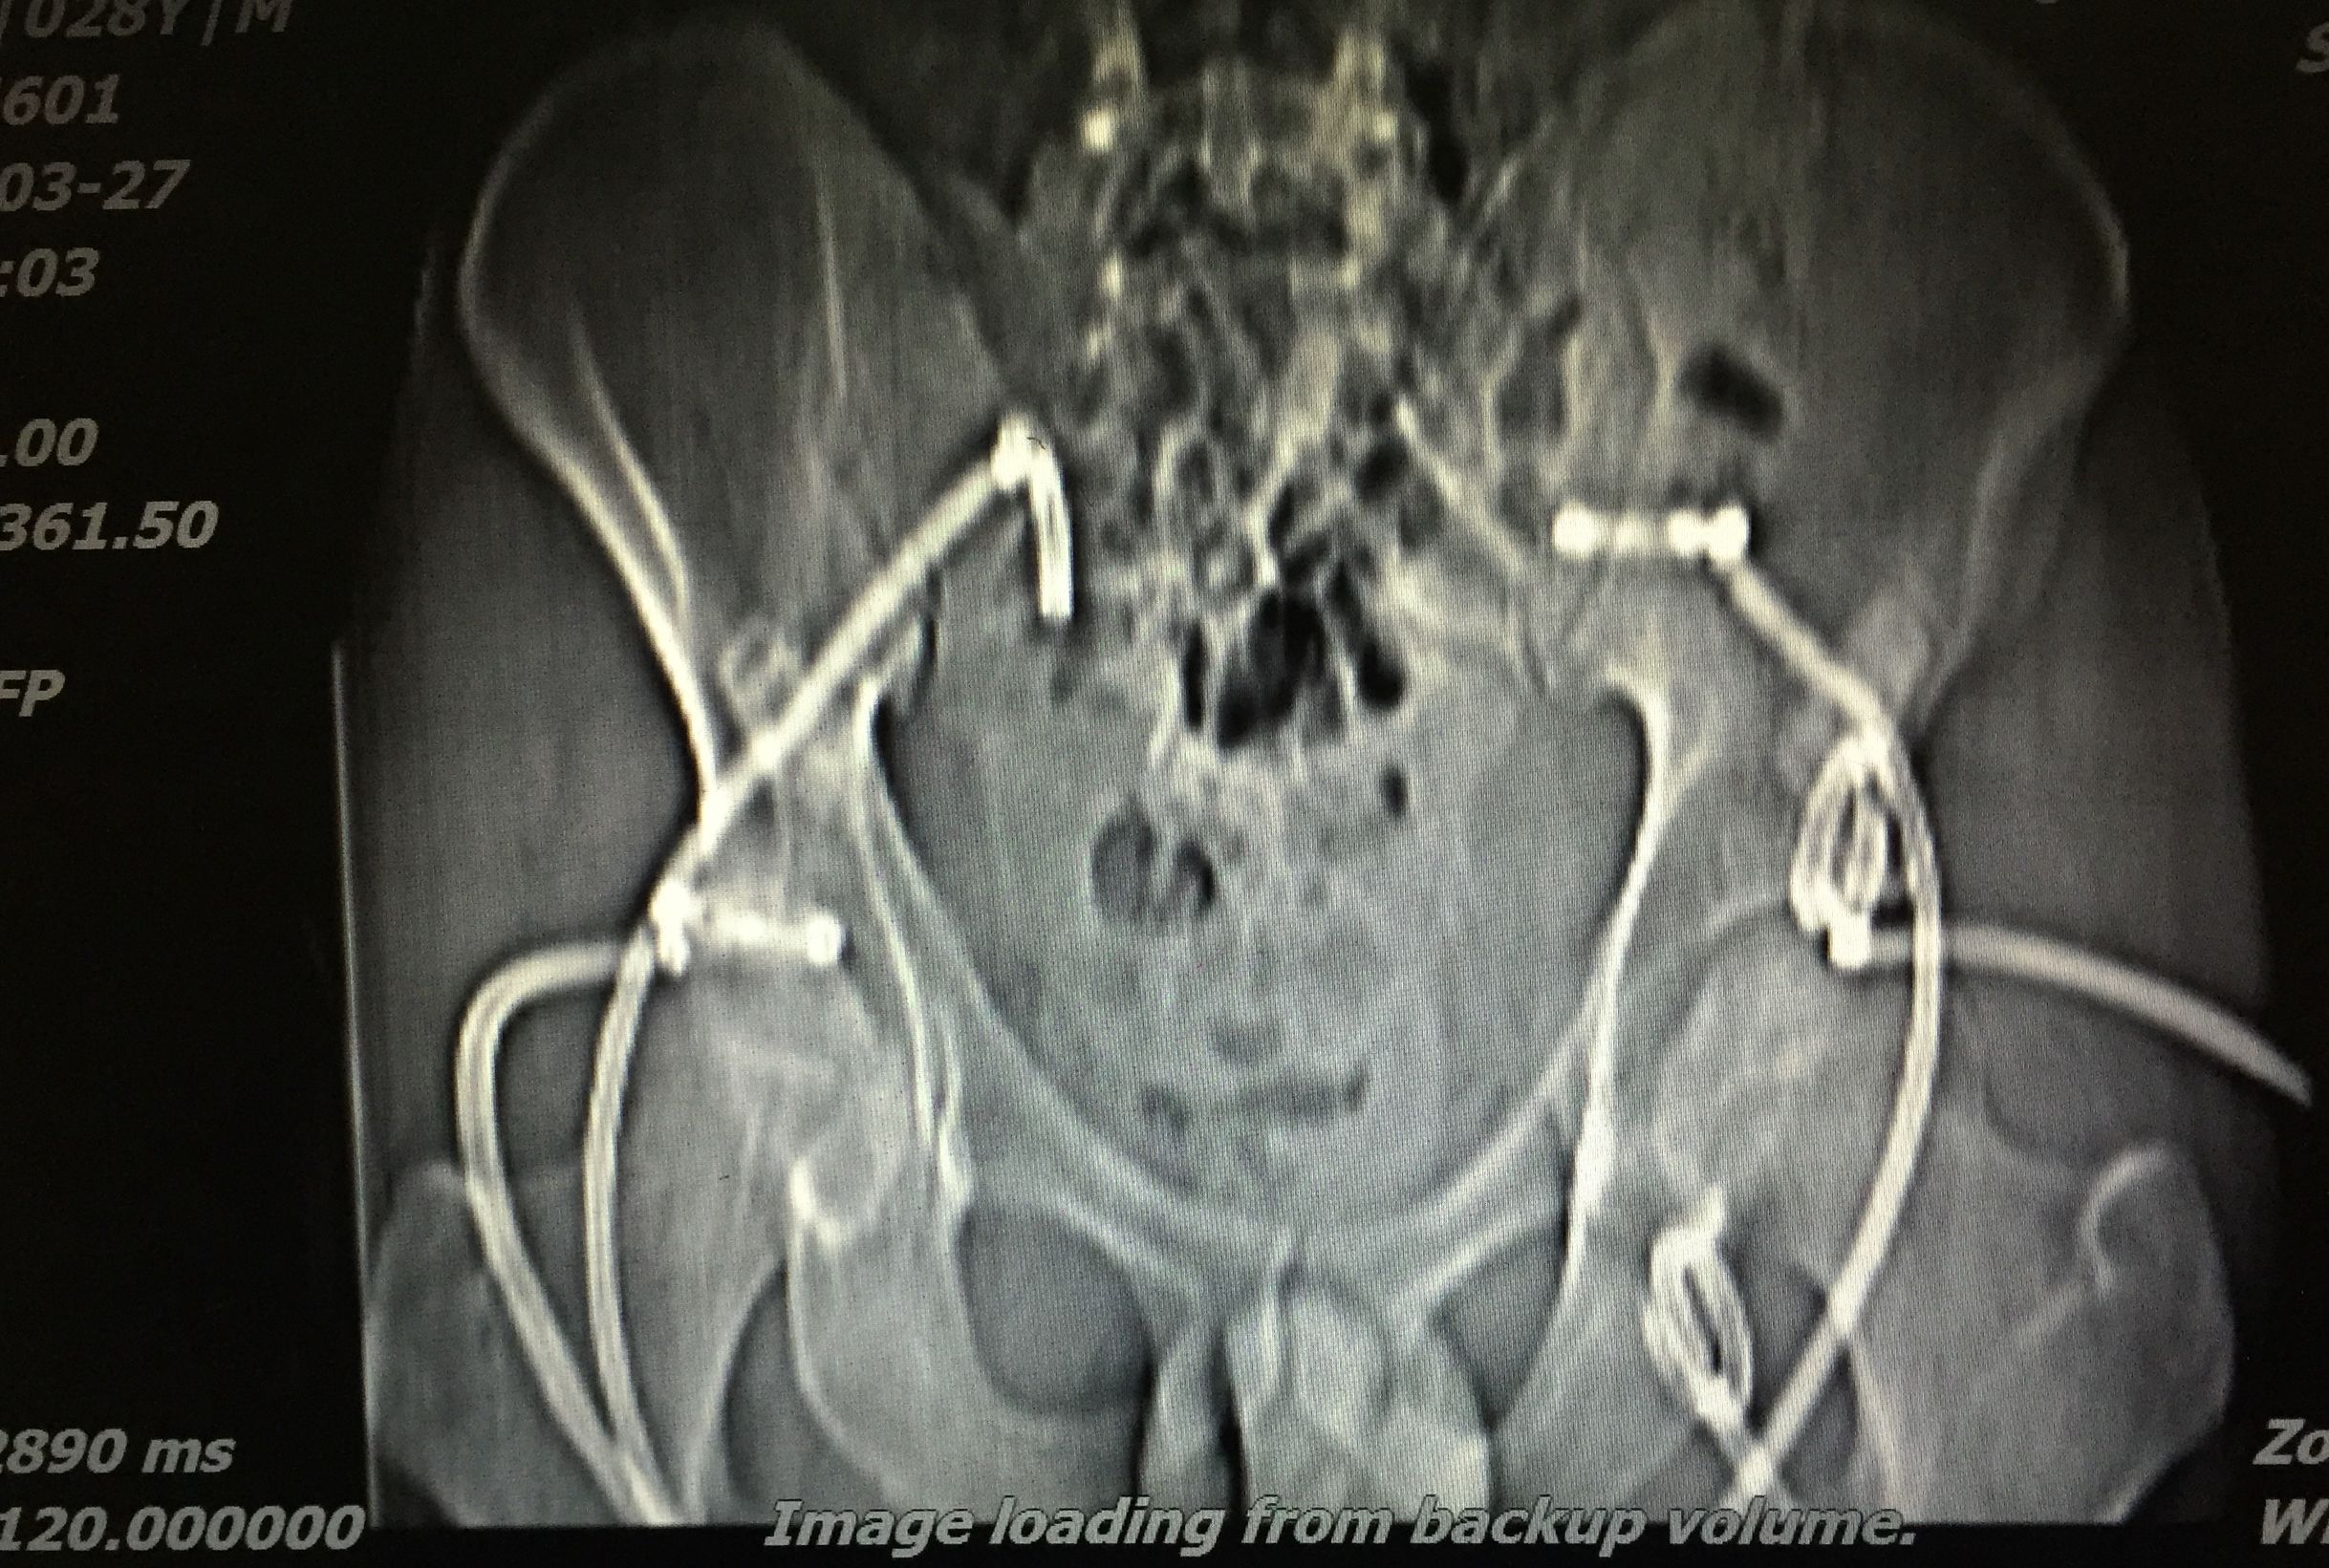

病例分享:1

患者 20岁,低热、盗汗半年余,腰骶部疼痛。CT显示盆腔多发结核脓肿,同时骶骨骨质基本破坏,骨盆力学结构受损。

我们对患者在门诊进行充份置管引流(白色条状物5根)

在患者持续引流状态下,并联合抗痨治疗。如下图所示,脓肿完全吸收。患者痊愈。